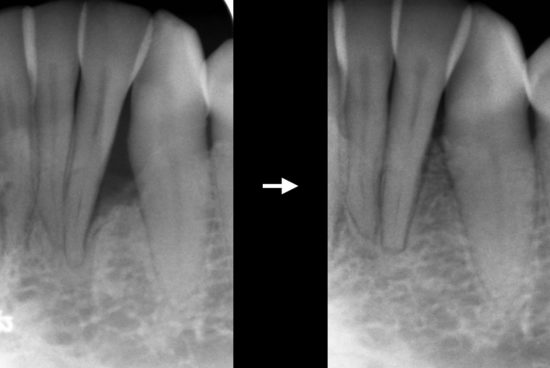

Dans les cas plus sévères de maladies parodontales, il peut rester des défauts osseux adjacent aux dents. Une approche régénérative est favorisée en guise de traitement, dans la mesure du possible. La régénération tissulaire guidée (RTG) fait appel à l’utilisation de techniques et de matériaux de pointe pour recréer une partie du tissu osseux perdu en raison de la maladie parodontale.

Radiographies démontrant la régénération de l’os adjacent à la racine de la dent